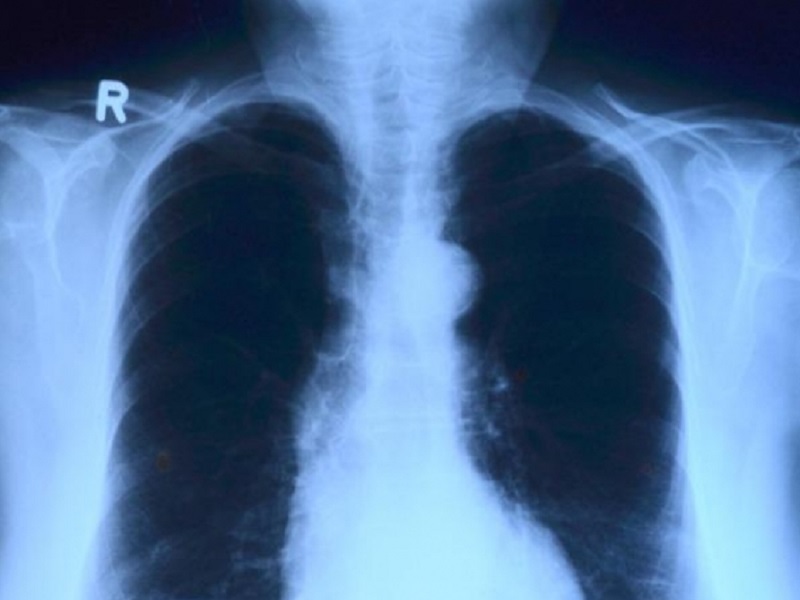

Le bronchiectasie, come è noto, rappresentano una condizione respiratoria cronica caratterizzata da evidenze radiografiche di dilatazione di alcune vie aeree respiratorie, associata alla presenza di tosse, produzione di espettorato e storia pregressa di esacerbazioni.